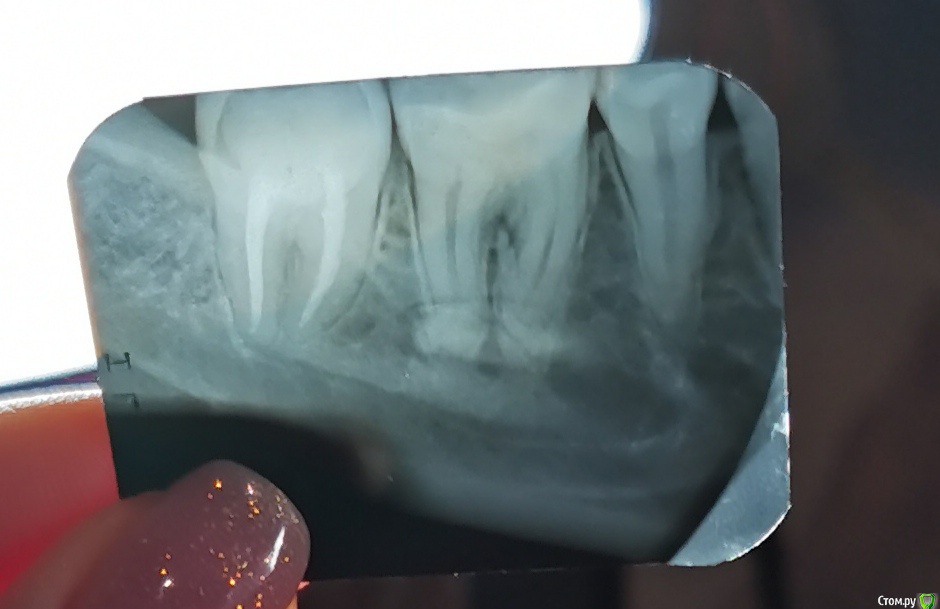

Ffgtrigun Опубликовано 22 июня, 2020 Поделиться Опубликовано 22 июня, 2020 Добрый деньПрошу совета:1) 03.06 назначили упражнения для шейного отдела. Одно из: ладонь на внешний угол челюсти, и наклонять голову, а ладонью устроить противовес. Через три дня, заболела нижняя челюсть с левой стороны, подумала, что порезала пломбой десну. Два дня понаблюдала, затем четыре дня прикладывала один раз в день тампон с мараславином на пять минут. Боль была тупая и тянущая, иногда пульсирующая, но терпимая, спать не мешала, при надавливание боль пропадала совсем, обезболивающие не принимала. 16.06 боль стала резкой, длительной , при смене положения тела боль усиливалась. Выпила 250 мг анальгина, купировалось хорошо.2) 17.06 Посетила дежурного стоматолога, после моей истории, решили, что само пройдет, но на всякий отравила на рентген (картинка 1). Вскрывают пульпу, ставят диагноз периодонтит, один канал сказали пустой, второй поковыряли иглой, но приговаривали, что тяжело пролезть и бояться обломать инструмент и бором с насадкой лезть не стали. Отправили с открытым зубом домой до пятницы ( ближайший талон 26.06), наказали полоскать чуть горячим содовым раствором 6-8 раз в день. После полоскания боль становилась невыносимой и длительно не утихала (при этом болело все на левой стороне снизу), пила анальгин. При смене положения тела боль также усиливалась.3) 22.06 обратилась к стоматологу, сделали еще один снимок(картинка 2). сказали, что корни и периодонтит залечить можно, каналы нужно пломбировать и у меня бифруктация, киста может расти, но залезть туда не смогут и полечить. Шансы, после очистки каналов, на сохранение зуба 50\50. Дальше понятно только удалять. Мне 28 лет и совершенно не хочется удалять. Подскажите, как увеличить шансы на спасения зуба? Стоит ли вкладывать в зуб или лучше уже деньги на вставной отложить? Я в г. Ульяновске может есть тут волшебник, что спасет зуб.И если можно на пальцах, как так могло получиться: посещаю стоматолога раз в полгода(она кстати не рада говорит, что можно и раз в год, поэтому стала ходить к разным) полоскаю полость рта после каждого приема пищи(нормальных приемов, после перекуса нет), пользуюсь раз в день зубной лентой(нить не подошла, близко зубы), приобрела ирригатор (десна правда с трудом привыкают), раз в год панорамный снимок или КТ. Мне обидно и страшно. Ссылка на комментарий

St. Опубликовано 22 июня, 2020 Поделиться Опубликовано 22 июня, 2020 Добрый день. Снимки не совсем хорошего качества.. но показаний к удалению зуба не увидела. Нужно качественно полечить каналы, в таком случае прогноз хороший.А удалить зуб всегда успеете, это крайняя мера когда других вариантов нет Ссылка на комментарий